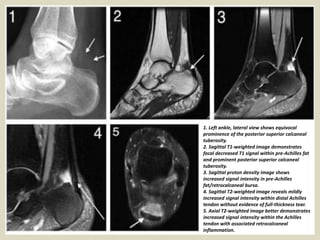

1. Left ankle, lateral view shows equivocal

prominence of the posterior superior calcaneal

tuberosity.

2. Sagittal T1-weighted image demonstrates

focal decreased T1 signal within pre-Achilles fat

and prominent posterior superior calcaneal

3. Sagittal proton density image shows

increased signal intensity in pre-Achilles

fat/retrocalcaneal bursa.

4. Sagittal T2-weighted image reveals mildly

increased signal intensity within distal Achilles

tendon without evidence of full-thickness tear.

5. Axial T2-weighted image better demonstrates

increased signal intensity within the Achilles

tendon with associated retrocalcaneal

inflammation.